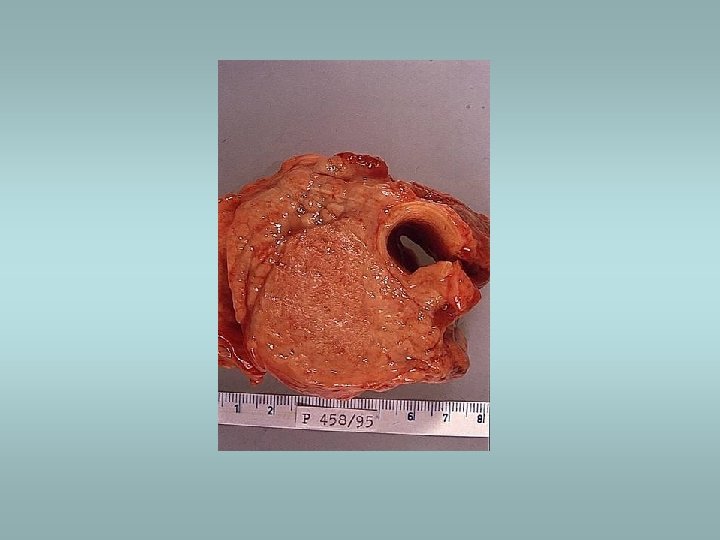

Tumors Benign – adenomas ü Well demarcated ü Fibrosis ü Haemorrhage ü Calcifications ü Hürtle cell adenoma - oncocytic ü Usually „cold“ Malignant - carcinomas ü See transparency

Thyroid gland ü Hyperthyroidism ü Hypothyroidism ü Goitre – focal, diffuse